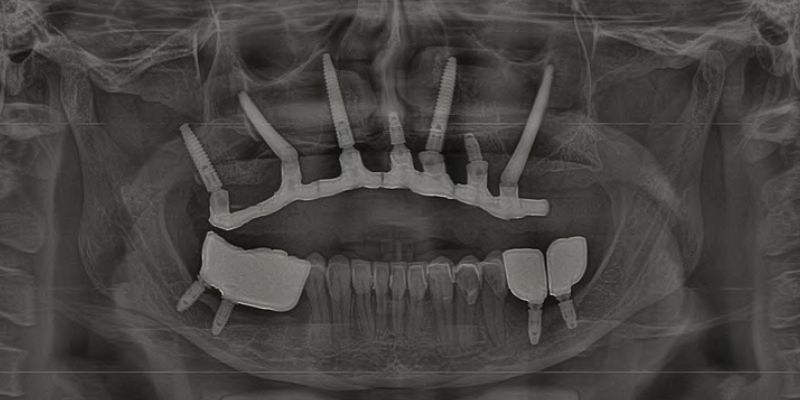

5. Técnica All on 4 ou All on 6

A técnica All on 4 (ou All on 6) consiste na instalação de quatro ou seis implantes em posições estratégicas da arcada dentária para sustentar uma prótese fixa. Essa abordagem é indicada para pacientes que perderam todos os dentes de uma arcada e oferece uma solução estética e funcional com carga imediata, transformando a vida dos pacientes em apenas um dia.

6. Implantes Zigomáticos Híbridos

Os implantes zigomáticos híbridos combinam implantes convencionais com implantes ancorados no osso zigomático. Essa técnica é utilizada em casos extremos de atrofia óssea na maxila e permite a reabilitação total sem a necessidade de enxertos ósseos.

7. Implantes Duplo Zigoma

Essa abordagem utiliza dois implantes em cada lado da maxila, fixados diretamente nos ossos zigomáticos. A técnica é ideal para pacientes com atrofia óssea severa e proporciona maior estabilidade e suporte para próteses fixas com carga imediata.